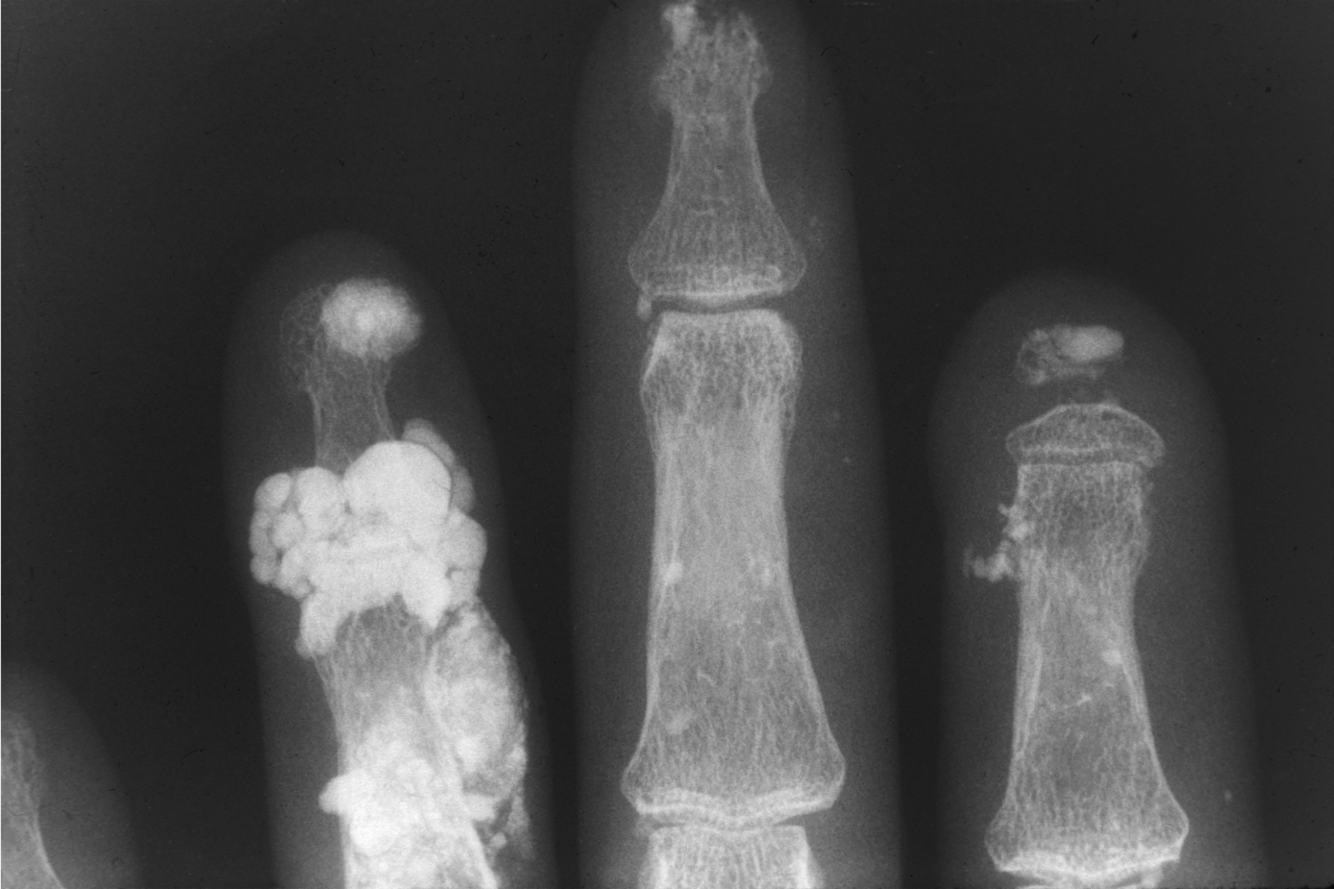

What is this? In what disease/type does it occur?

What are possible complications?

Calcinosis.

Get this with Systemic Sclerosis - Limited type (NOT diffuse type)

Complications: necrosis, infection possible.

No treatment.

What is this? What disease/subtype is it associated with?

Systemic Sclerosis - Limited type.

May have resorbtion of the bone (acro-osteolysis)